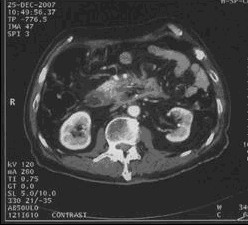

男,68岁,2006年12月14日,CT扫描发现胰头占位性病变,6.0×4.7cm2,腹膜后淋巴结转移,伴肝内多发转移灶。艾恒+希罗达化疗3疗程无效(图1)。2007年4月5日,开始接受今又生治疗,胰腺肿瘤内注射今又生1×1012VP,共2次,结合放疗45Gy/10f(图2)。2007年5月12日,IMA64+C,5.3×3.5=18.6cm2,缩小41.0%,瘤囊性化。腹腔灌注今又生5次,1-2×1012VP/次/周,+顺铂60mg,健择每周1.4g,治疗2周。疗后1年,肿瘤进一步缩小及坏死(图3)。

治疗后